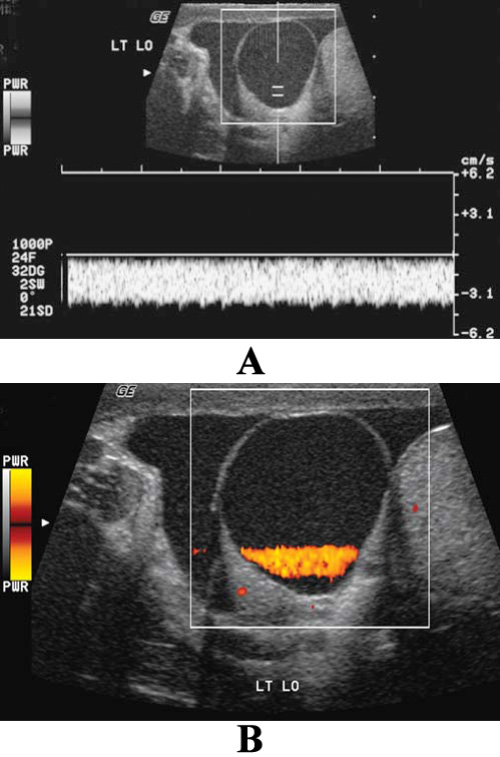

Фото 4. УЗИ органов мошонки: артефакт ложного потока. А – продольное изображение верхнего отдела яичка и придатка с кистой: на цветной допплерограмме интенсивно окрашенная полоса заполняет часть кисты. В – спектральная допплерограмма демонстрирует монотонный однонаправленный поток, позволяющий определить движение жидкости или взвеси в самой кисте